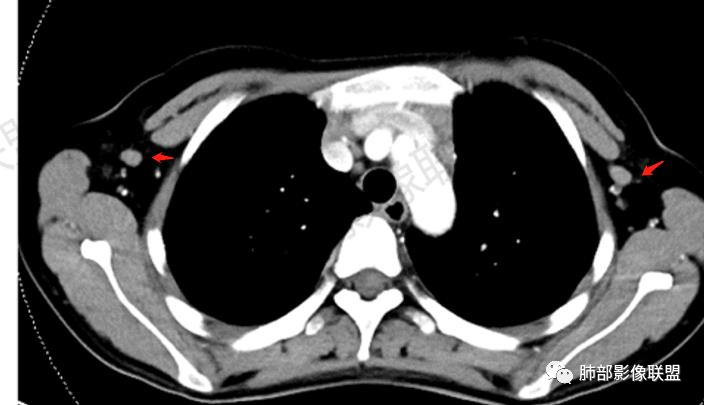

2.影像显示前纵隔不规则块状影,依势贴附心脏大血管旁,密度不均,边界不甚清楚,有结节融合感。

3.病灶轻度不均匀强化,可见血管穿行,散在液性低密度区。

双肺门未见肿大淋巴结。

4.双侧腋窝区见增大淋巴结,边界清楚。